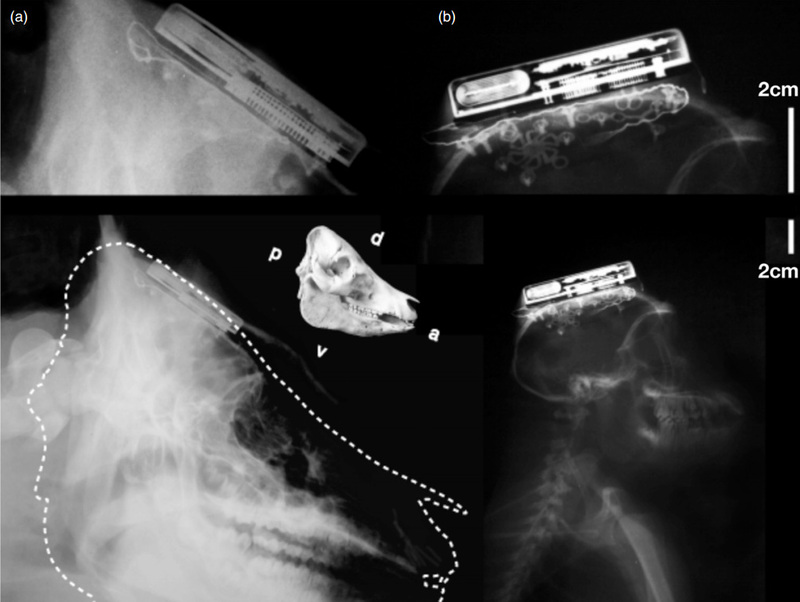

Учёные из Brown University создали первый в мире беспроводной имплантируемый компьютерно-мозговой интерфейс (КМИ). После 13 месяцев тестирования на обезьянах и свиньях оно готово к тестированию на людях.